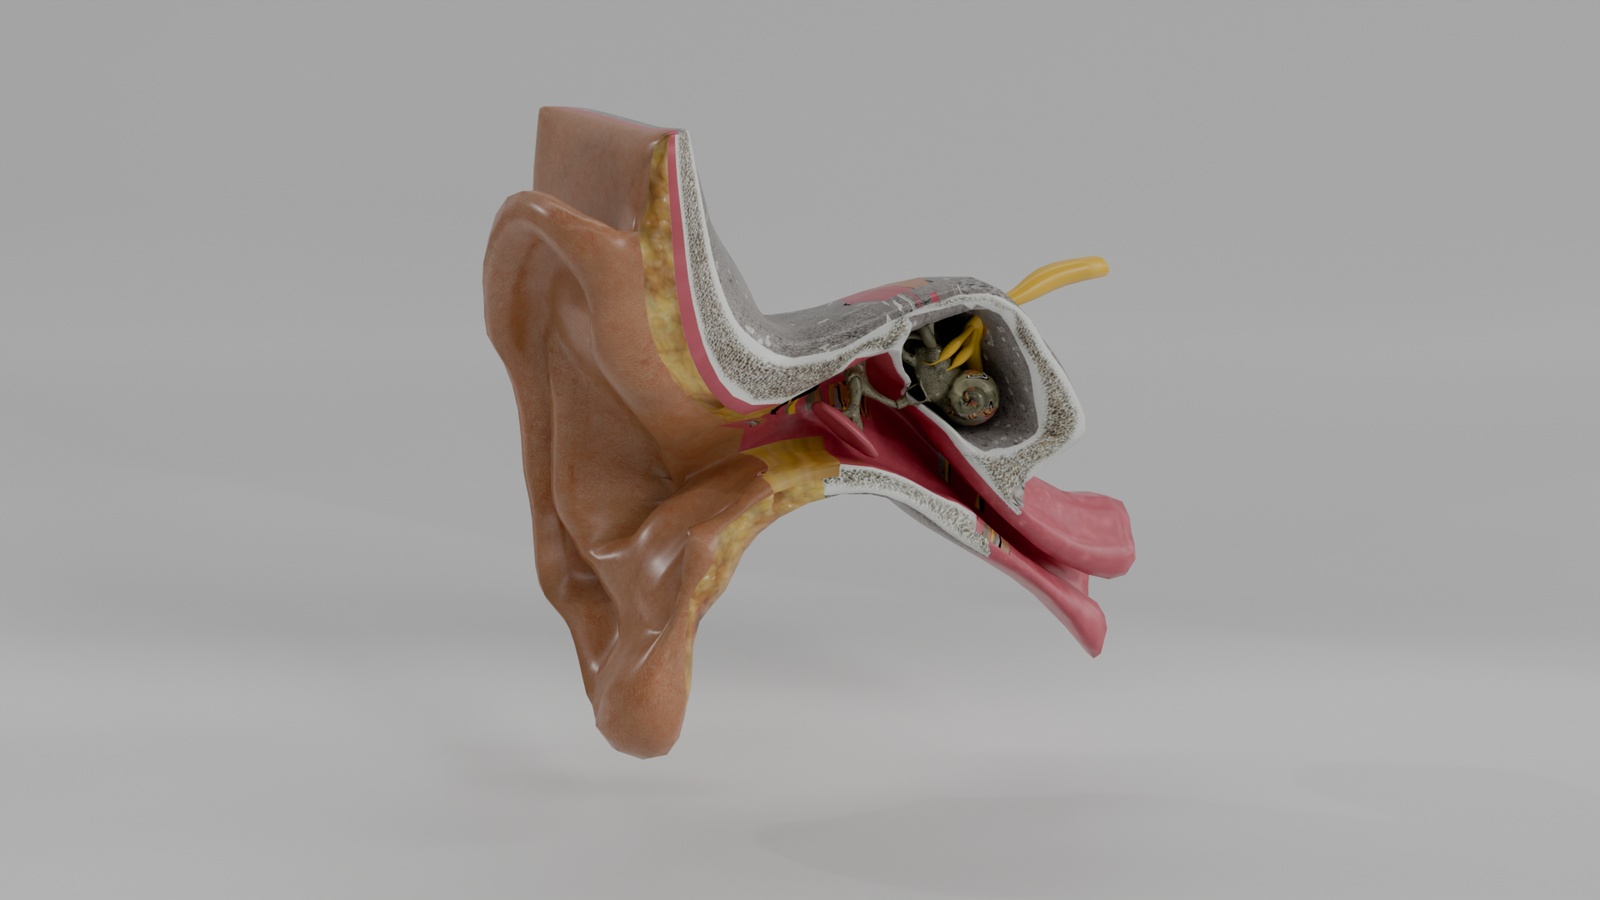

Oído Humano

Modelo 3D educativo